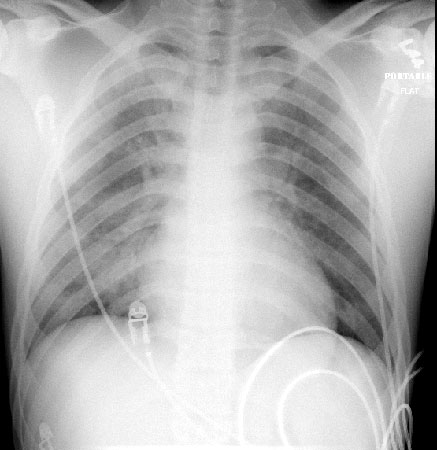

The CXR may be normal, especially in children, if laryngospasm (diving reflex) occurs. Otherwise, a "batwing" pattern of pulmonary edema is seen. The situation may be complicated by ARDS.

PA of near drowning patient after resuscitation